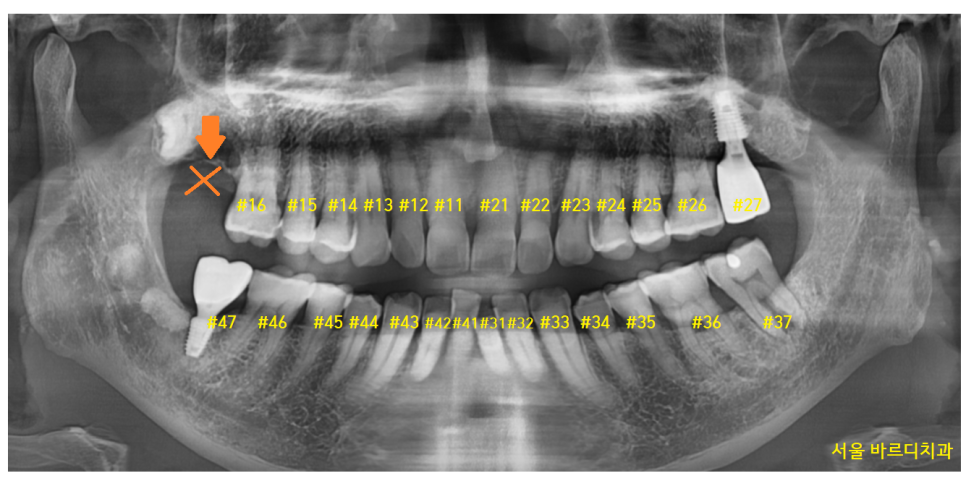

23.01.12

치아 개수가 하나가 비죠~?

오른쪽 맨 위 치아가 빠진 환자분입니다.

구강 내 사진을 보겠습니다.

#17 맨 끝 어금니가 한 개가 없네요.

이 경우에는 교합을 확인합니다.

23.03.12

#47 오른쪽 아래 맨 끝에 치아가

#16 오른쪽 제 1큰 어금니와 물리네요.

#17 맨 뒤에 치아가 없지만

물리기 때문에

이 경우는 임플란트를 안 해도 됩니다.